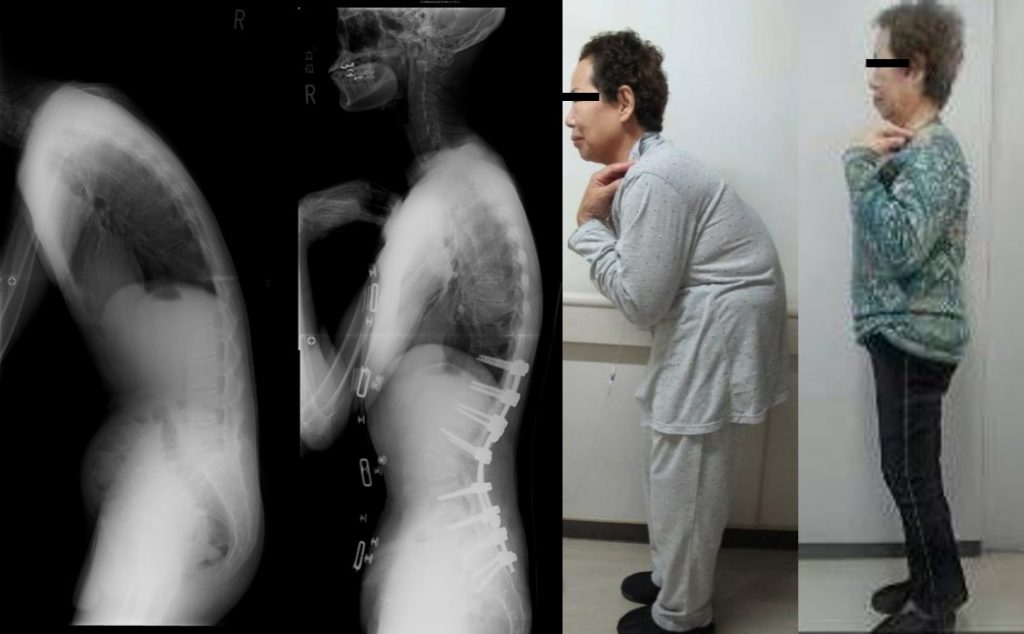

腰椎変性後弯症(LDK)は、高齢者によく見られる脊椎の病気です。脊椎の骨と筋肉の変性変化による腰部の異常な前方湾曲を特徴とします。

この状態は、多くの場合、腰や脚の痛み、顕著な猫背の姿勢を引き起こします。

手術は、歩行困難、持続的な痛み、または他の治療法では改善しない深刻な姿勢の問題などの重度の症状のある人に検討されます。

研究によると、手術前に横たわった状態で骨盤の傾き(仰臥位骨盤傾きまたはsPT)を測定することが重要です。 sPT と術後の骨盤の傾きの間に大きな差がある場合、術後の問題につながる可能性があります。

sPT を適切に評価することは、医師が手術をより適切に計画するのに役立ち、合併症のリスクを軽減します。